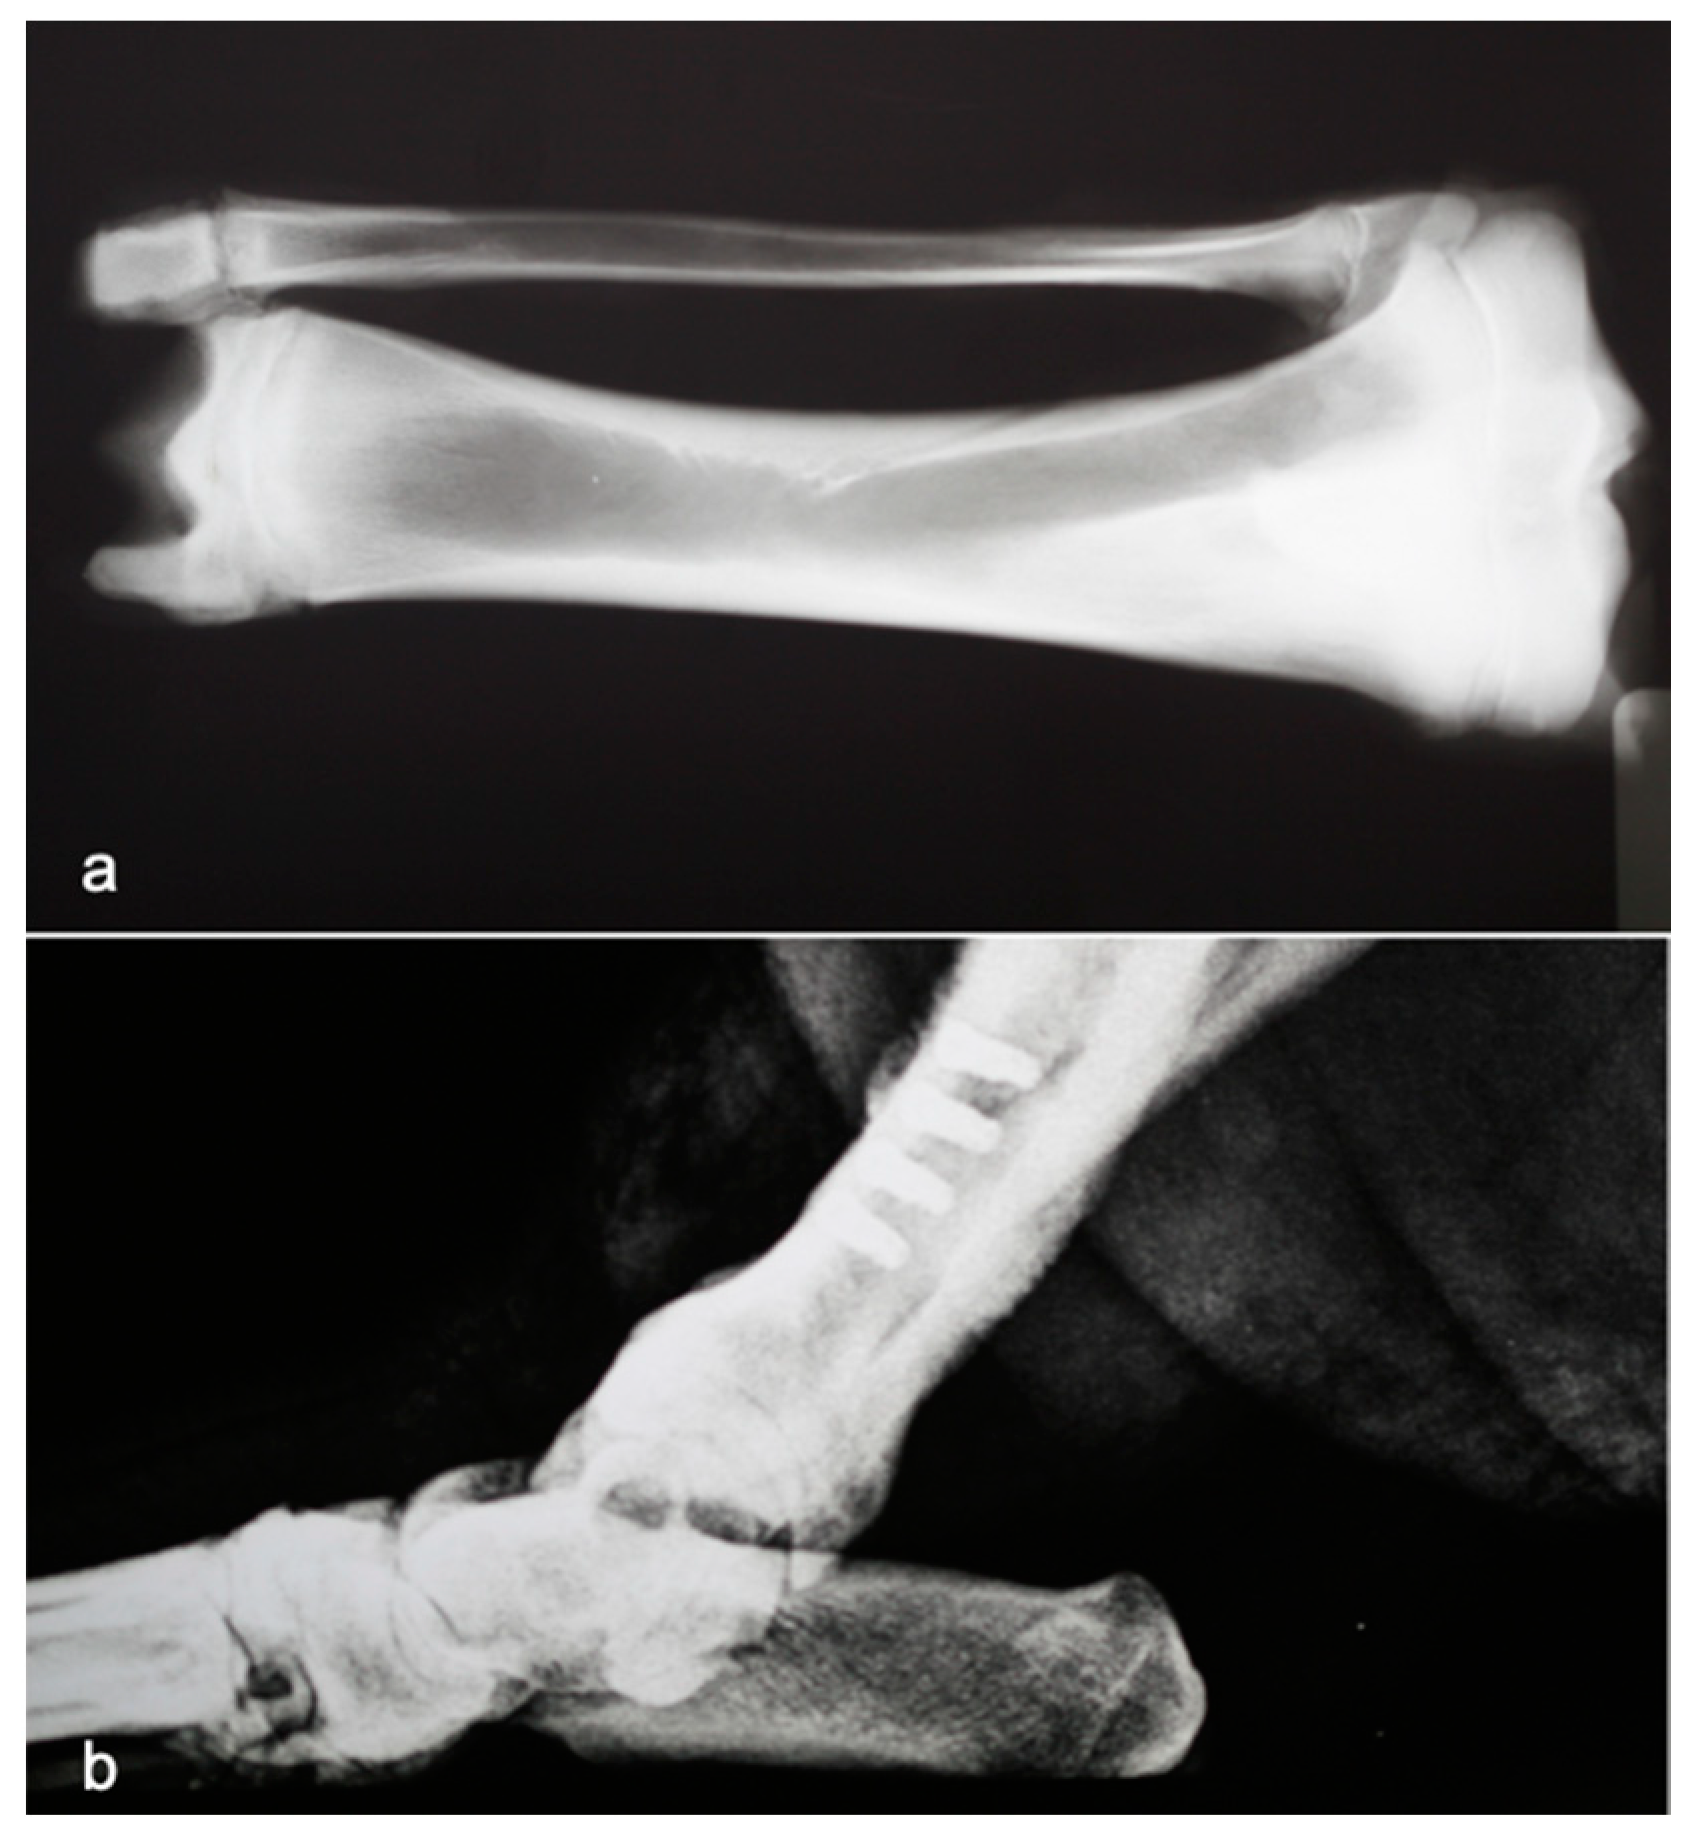

2.2. Implant Insertion

3.1. Histological Analysis